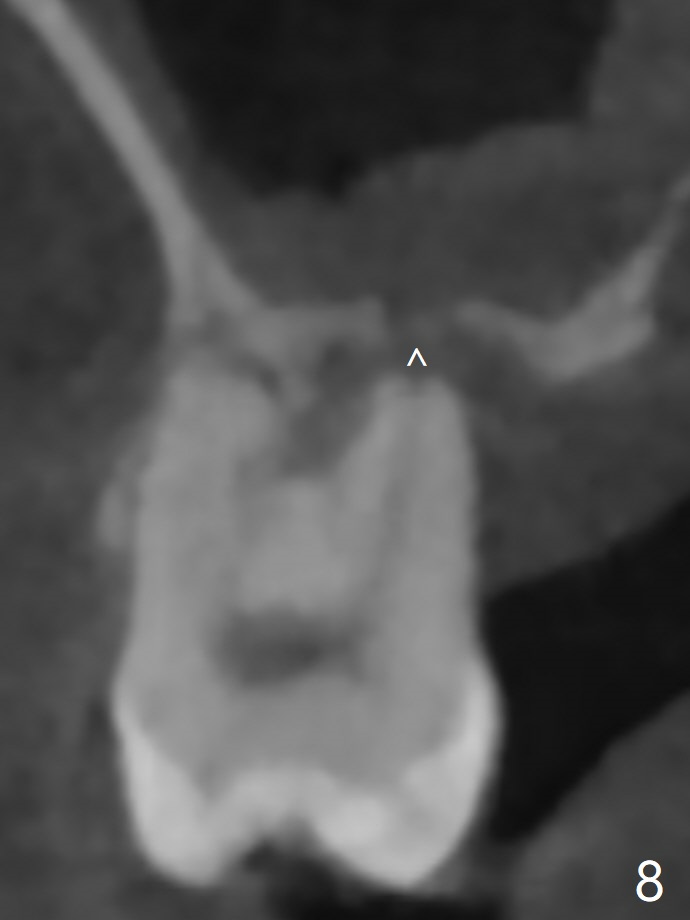

45岁女右上7严重骨质吸收终于开始出现症状(图一),虽然邻牙(6)骨质吸收也明显(图二,四,六,八,十),但是保留它,远中颊侧(DB),腭侧(P)根成为骨粉(图三,五,七,九,十一:红圆圈)支架。